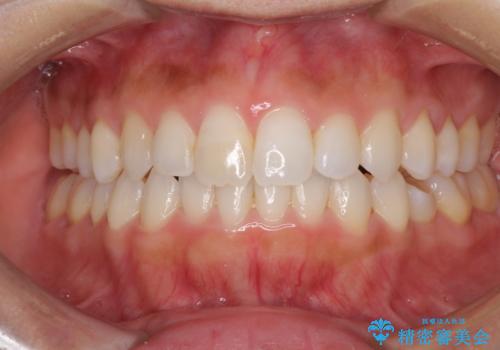

- 上下の前歯のデコボコと奥歯の反対咬合を気にして来院された患者様です。

インビザラインを用い、上下顎ともにIPR(歯と歯の間を削る)により叢生を改善することとしました。

治療を長期化させたくないとのご要望があったので、左下の90度捻転した歯は、捻転した状態のゴールとしました。

反対咬合を改善したことで、歯ぎしりしたときの引っかかる感じがなくなり、奥歯への負担を大きく軽減することができました。